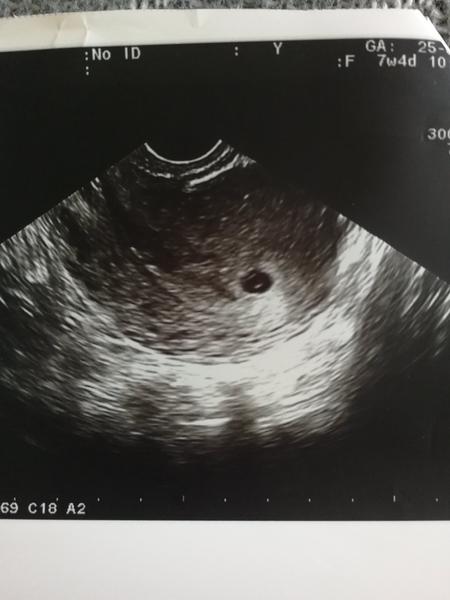

Ahojte baby dnes som bola na gynde lebo som trosku zaspinila rano. Robili mi odbery aj sono, hcg som mala vyse 10 000 a na sone mi oznacilo 5tt+2 a zatial vidiet len gestacny vacok a zltkovy vak. Myslíte ze je to ok? To hcg sa mi zda vysoke na 5tt+2. Ci? Plodik zatial nebol vidiet co je vraj normalne, az od 6tt by mal byt vidiet.